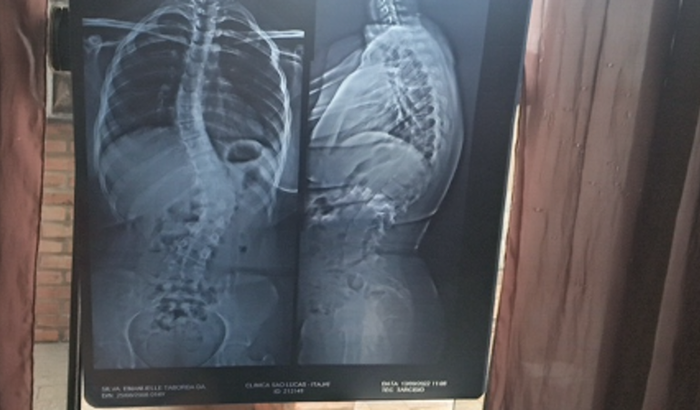

Criei essa Vaquinha para conseguir dar continuidade no tratamento da minha filha, ela está com ESCOLIOSE GRAVE, de 36,8° graus a esquerda, como mostra o raio X, está na fila de espera para a Cirurgia de Urgência pelo SUS. Como ela sente fortes dores diariamente o médico indicou fisioterapia com especialidade em RPG, tratamento que o SUS não atende, e o uso contínuo do COLETE MILWAUKEE, que tem um custo bem alto, consegui pagar consultas e o raio X dela, mas não tenho como arcar com o restante do tratamento que é bem caro, e no momento estamos com dificuldades financeiras. dúvidas contato 47 9 9932- 4829